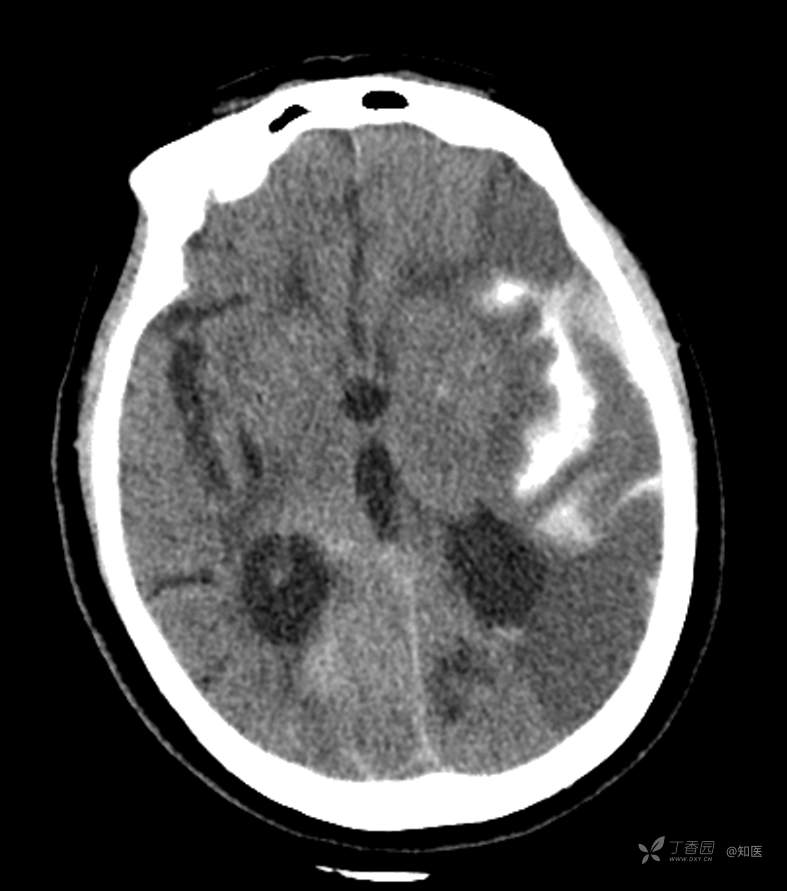

4-22日查房患者呈昏睡状,混合性失语,右侧肢体肌力障碍较入院时加重,胃肠减压引流物为深黄绿色液体,量约150ml。查体:GCS 9分(睁眼反应 3分+语言 1分+运动 5分),NHISS评分23分(意识水平 2分+提问 2分+指令 1分+凝视 2分+面瘫2+左上肢 1分+右上肢4分+左下肢 2分+右下肢4分+语言 3分),昏睡状,查体欠合作,混合性失语,粗测智能查体不配合。双眼闭目紧,双侧球结膜水肿,双侧瞳孔等大等圆,直径约4.0mm,对光反射灵敏,眼球无自主运动,无眼震,右侧鼻唇沟浅,口角向左歪斜。咽部查体不配合。转颈、耸肩查体不配合。伸舌不配合。右上肢肌力1级,右下肢肌力2级,左上肢肌力3级,左下肢肌力4级,四肢肌张力减低。四肢深浅感觉及共济运动查体不配合。右侧巴氏征阳性,左侧巴氏征阴性。颈抵抗。双侧布氏征及克氏征均阴性。辅助检查:头颅+胸部CT:与前片(2021-4-21 13:57)对比,现片示:1、环池、桥前池及大脑镰后部及小脑幕高密度影,考虑出血,较前新发。2、额颞顶叶高低混杂密度影,考虑梗塞伴造影剂残留;左侧大脑中动脉走行区致密影,系术后改变;请结合临床。3、多发腔梗,脑白质脱髓鞘,脑萎缩。4、双肺间质性改变,双肺下叶纤维索条,双侧胸腔微少量积液征象,双侧胸膜增厚。5、主动脉及冠状动脉管壁多发钙化斑块。三线主任医师、二线主治医师查房后示:根据患者病史、体征及辅助检查,目前诊断:1.脑梗死出血转化;2.左侧大脑中动脉次全闭塞;3.左侧大脑中动脉支架植入术后;4.高血压2级(很高危);5.2型糖尿病;6.应激性溃疡伴出血。目前病情及治疗上需注意以下问题:1.患者出血转化,增加脱水剂剂量,调整为20%甘露醇 125ml 每8小时一次、甘油果糖 250ml 每12小时一次,同时结合患者球结膜水肿,白蛋白正常低值,今日给予补充人血白蛋白10g,注意监测电解质等变化。2.患者为蛛网膜下腔出血,给予泵入尼莫地平预防脑血管痉挛。3.患者左侧大脑半球见大片脑白质脱髓鞘,考虑脑白质营养不良,给予维生素B1、维生素B12、维生素C、维生素B6及依达拉奉改善微血管通透性;4.患者出现应激性溃疡伴出血,今日暂禁食,给予泮托拉唑抑酸及肠外营养补充,密切观察消化道出血情况,根据病情变化调整抑酸药物剂量及频次;5.患者卧床,今晨见明显痰多,给予化痰等对症处理,监测血常规及脓毒症2项指标。6.向家属再次告知病情,因患者高龄、既往高血压及糖尿病病史,此次治疗出现出血转化,存在意识障碍加深、病情加重可能。7.密切观察神经系统体征变化。遵嘱执行。

4-23日查房:患者呈中度醒状昏迷,右侧肢体肌力障碍较入院时加重,胃肠减压引流物为黄绿色液体,量约200ml。入院后至今晨入量为4050ml,出量为4850ml。查体:GCS 6分(睁眼反应 2分+语言 1分+运动 3分),NHISS评分35分(意识水平 3分+提问 2分+指令 2分+面瘫3分+左上肢 4分+右上肢4分+左下肢 4分+右下肢4分+感觉 2分+语言 3分+构音障碍 2分+忽视 2分)。中度昏迷。双目睁眼状,双侧球结膜水肿较昨日明显,双侧瞳孔等圆,不等大,右侧直径约3.5mm,左侧瞳孔直径约3.0mm,对光反射灵敏,眼球无自主运动,无眼震。右侧鼻唇沟浅,口角向左歪斜。咽部查体不配合。转颈、耸肩查体不配合。伸舌不配合。四肢肌力检查不配合,右上肢落鞭征阳性,左上肢落鞭征阴性,右下肢不能撑于床面,左下肢可撑于床面,四肢肌张力减低。四肢深浅感觉及共济运动查体不配合。右侧巴氏征阳性,左侧巴氏征阴性。颈抵抗。双侧布氏征及克氏征均阴性。辅助检查:经颅多普勒示:左侧大脑中动脉峰值流速极低,右侧大脑中动脉及双侧大脑前动脉血流速度未见明显异常。头颅CT(2021-04-22):与前片(2021-4-21)对比,现片示:1.环池、桥前池及大脑镰后部及小脑幕高密度影,较前减少。2.额颞顶叶高低混杂密度影,考虑梗塞伴造影剂残留;左侧大脑中动脉走行区致密影,系术后改变;基本同前。请结合临床。3.多发腔梗,脑白质脱髓鞘,脑萎缩。同前。二线主治医师查房后示:患者目前诊断明确。现治疗上需注意以下问题:1.患者夜间体温上升,最高38度,结合患者卧床、痰多、不易咳出,且化验检查提示炎性指标较前明显升高,今日给予头孢哌酮舒巴坦抗感染治疗,同时继续雾化祛痰等。2.因患者应激性溃疡并出血,昨日查胃液潜血阳性,但经给予泮托拉唑抑酸护胃治疗后消化道出血未进行性加重,胃管引流物为黄绿色液体,今日暂继续给予氨基酸、脂肪乳等肠外营养支持,安排再次复查胃液潜血,若转阴可给予肠内营养加强支持治疗。3.患者血压仍有偏高,夜间泵入乌拉地尔控制,今日给予左氨氯地平平稳控制血压,监测血压变化。4.患者昨日血糖波动在6.8-11.4mmol/l,结合其糖化血红蛋白为6.4%,暂不干预血糖,继续监测血糖变化。5.患者意识障碍程度加重,双侧瞳孔不等大,但光反射灵敏,考虑与脑梗死后水肿高峰有关,治疗上继续加强脱水,向家属再次详细告知病情及目前诊疗方案,存在颅内压增高至脑疝形成、呼吸心跳骤停可能,表示理解知情。密切观察生命体征及神经系统体征变化。遵嘱执行。